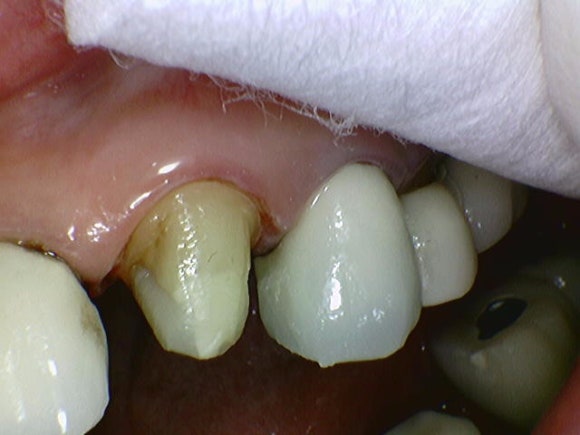

구강카메라로 즉시 확인해보니,

아뿔싸,

치태와 치석 아래 숨어있던 충치가

이제야 모습을 드러내네요.

주기적인 스케일링과 잇몸치료(40대 이상)은

이처럼 중요합니다.

엑스레이로도 찾지 못하는 충치를 조기에 발견하게 해주거든요.